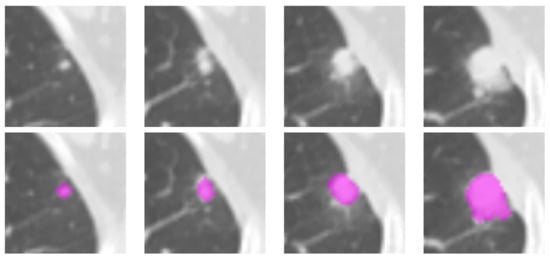

2.2. Lesion Delineation

2.3. Shape Features